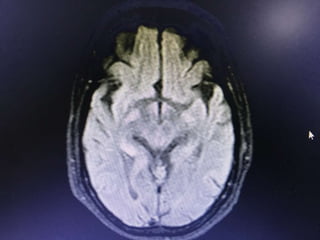

Investigations

• HB- 14.1gm% - 12.2

• WBC- 15990cells/cumm - 10770, -P 83%, L-9%,M-7%

• Platelets - 3.3lakhs - 2.8

• ESR- 63mm/hr

• RBS - 267 mg/dl

• CUE - N

• RFT - N

• LFT - N

• S.Na - 137, k+ - 3.9, Mg- 2.1, Ca- 9.1, Ph- 3.5, Ammonia- 0.29

• ECG - N

• 2DEcho- N

• U/S - Abd- Gr I Fatty liver changes

Investigations • HB- 14.1gm%- 12.2 • WBC- 15990cells/cumm - 10770, -P 83%, L-9%,M-7% • Platelets - 3.3lakhs - 2.8 • ESR- 63mm/hr • RBS - 267 mg/dl • CUE - N • RFT - N • LFT - N • S.Na - 137, k+ - 3.9, Mg- 2.1, Ca- 9.1, Ph- 3.5, Ammonia- 0.29

• 9.

• ECG -N • 2DEcho- N • U/S - Abd- Gr I Fatty liver changes